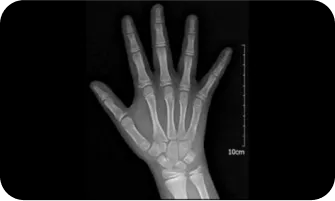

03

골반 엑스레이 검사 (risser sign) 검사로 성장 정도 파악

Risser 0

Risser 1

Risser 2

Risser 3

Risser 4

Risser 5